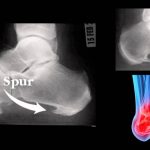

Для основательного заключения что имеется пяточная шпора, рентген делают обязательно. Во время процедуры оценивается размер и точное месторасположение заболевания на пятке. Не единожды, делая снимки по диагнозу ревматоидный артрит, случайно обнаруживали шипы на пятках. Пациент при этом не испытывал никакого дискомфорта от шпоры на пятке.

Рентген показывает шип, расположенный на пяточном бугре. Пяточные шпоры изогнуты к пальцам, часто достигают 12 мм. При этом они напоминают клюв птицы. На ранней стадии шпора на пятке округлая. Иногда для определения шпоры на пятках делают МРТ. УЗИ используют не так часто. Его проводят, в основном, для лечебного контроля.